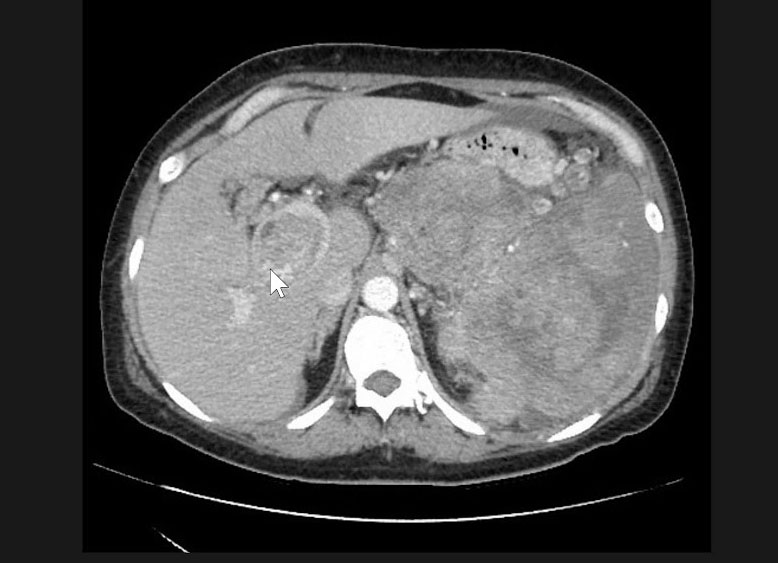

- tomografia com cortes finos para pâncreas com protocolo trifásico observa massa heterogênea, hipocontrastante em relação ao pâncreas ao redor, atrofia da glândula e dilatação do ducto de wirsung e hepatocolédoco. Ela permite estadiamento para avaliar a invasão de vasos importantes como artéria mesentérica, tronco celíaco, veia mesentérica-porta; além de gânglios linfáticos e metástases hepáticas (fígado) ou peritônio;

- tomografia e ressonância. Como os PNETS são altamente vascularizados costumam se apresentar como tumores hipercontrastantes após administração de contraste na fase arterial apresentando coloração mais clara que o pâncreas ao redor tanto na tomografia quanto ressonância. Também pode ser realizados: o Octreoscan (Cintilografia com receptores para Octreotide) e a Cintilografia com Gálio 67;

Metastases são raras e correspondem a 2 % de todos canceres pancreáticos oriundas do câncer colorretal, pulmões, mama e melanoma. A maioria é assintomática e é descoberta por exame de imagem. Em geral, são altamente vascularizados costumam se apresentar como tumores hipercontrastantes após administração de contraste na fase arterial apresentando coloração mais clara que o pâncreas ao redor tanto na tomografia quanto ressonância. A biopsia por eco-endoscopia com punção pode dar diagnóstico, mas não é necessária na lesão isolada.